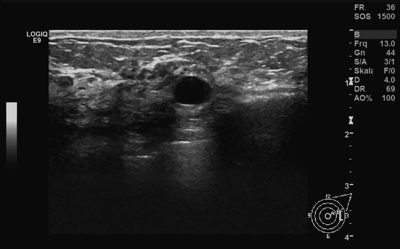

Der Ultraschall oder die Sonographie wird häufig als Ergänzung zur Mammographie - zumeist wegen Ihrer Brustdichte - durchgeführt. Im Gegensatz zur Mammographie arbeitet der Ultraschall nicht mit Röntgenstrahlung, sondern auf Basis von Schallwellen.

Durch diese grundsätzlich andere Arbeitsweise können im Ultraschall Bildungen sichtbar werden, die in der Mammographie vorallem durch eine dichte Brust schlecht erkennbar oder gänzlich verborgen sind. Überdies kann im Ultraschall ein in der Mammographie sichtbarer Knoten näher klassifiziert werden.